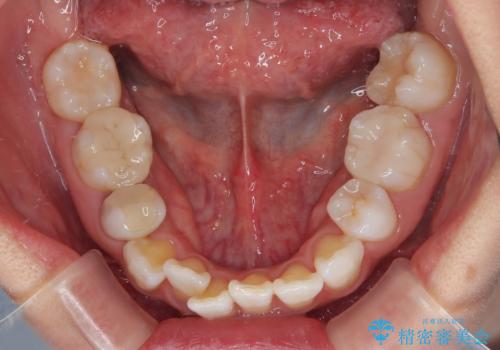

- 上下前歯の後戻りを気にして来院された患者様です。

インビザラインでの治療を希望されていて、デコボコの程度が中等度であり、安価なパッケージにて対応可能と判断されたため、インビザライン・モデレートを用いて矯正治療を行うこととしました。